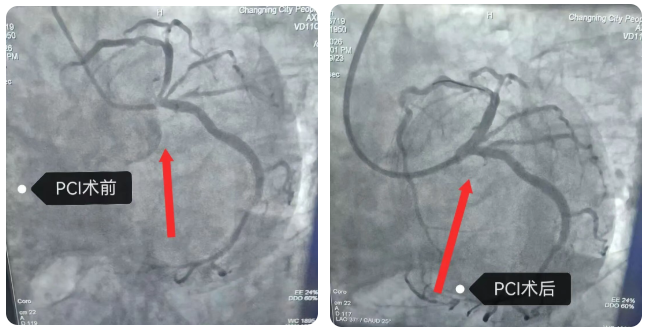

我院介入手术团队当机立断,立即为胡奶奶实施左主干病变介入治疗(PCI),成功开通罪犯血管并植入支架一枚。造影显示支架贴壁良好,血流TIMI3级。胡奶奶生命体征平稳,胸痛症状明显缓解,转入病房继续治疗。据悉,我院已经获批通过2026年第一批次胸痛中心再认证。此次认证通过,是国家胸痛中心对我院胸痛救治体系科学性、高效性的认可。医院将以此次再认证为契机,进一步推动区域胸痛救治网络建设,让更多患者在家门口就能享受到规范、高效的胸痛救治服务。